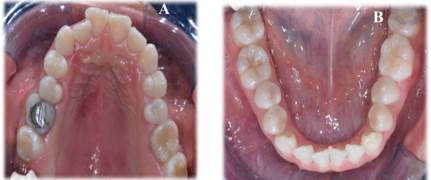

Descripción de caso clínico, paciente mestizo de sexo femenino, de 19 años de edad, llega a consulta, en la primera cita, se identificó clínicamente un prognatismo mandibular y una asimetría facial evidente en la paciente (Figura 1). Para confirmar y complementar el diagnóstico, se solicitaron estudios de imagen, consistentes en una radiografía panorámica, un análisis cefalométrico y una serie de fotografías intraorales y extraorales (Figura 1, Figura 2 y Figura 3).

Figura 2 Fotografías intraorales A: Oclusión Vista lateral derecha B: Oclusión Vista lateral izquierda C: Oclusión vista frontal

Asimismo, mediante la radiografía panorámica se confirmó la presencia de una laterognasia mandibular hacia el lado derecho, responsable de la asimetría facial marcada en la paciente. Estos hallazgos fueron determinantes para planificar el abordaje ortodóncico y quirúrgico adecuado. Se empleó un flujo digital para el diagnóstico y la planificación del tratamiento, lo cual incluyó la integración de escaneos intraorales, y análisis cefalométricos digitales. Esta tecnología permitió una evaluación tridimensional precisa de las estructuras óseas y dentales, facilitando un diagnóstico más detallado y la simulación del plan quirúrgico y ortodóntico, asegurando una mayor predictibilidad en los resultados clínicos.

Posterior a un año de tratamiento ortodóntico postquirúrgico, se evidencian resultados clínicos significativos en la paciente, una correcta alineación y nivelación de las arcadas dentarias con una notable oclusión funcional. La relación molar y canina se ha estabilizado, alcanzando un equilibrio oclusal contribuyendo a la funcionalidad masticatoria. Una mejora notable de la asimetría facial disminuyendo considerablemente, reflejando una armonía facial mejorada, gracias a la corrección del prognatismo mandibular y la reposición ósea lograda con la cirugía ortognática. La paciente reporto una notable mejora en la función masticatoria y en la estética facial, lo que ha contribuido a su calidad de vida (Figura 6).